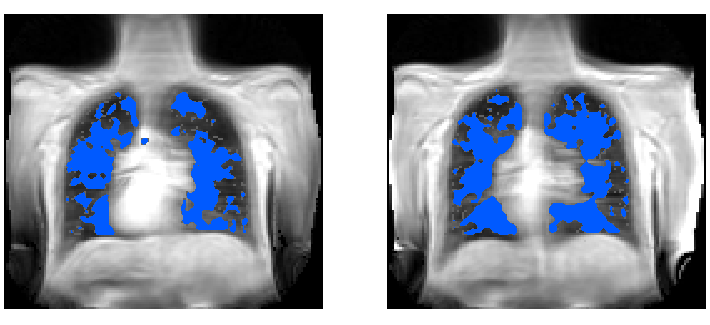

From study design to final reporting, Bioxydyn delivers repeatable MRI biomarkers that reveal tissue function, physiology and change. Our operational excellence and metrology help you compare results across sites, scanners and timepoints.

We're Bioxydyn - delivering quantitative MR biomarkers for pharmaceutical, biotech and academic studies. We combine scientifically leading methods with robust multi-centre study management and transparent analysis, turning complex images into repeatable measurements that support confident decisions.

Disease areas and services supporting quantitative MRI biomarkers across clinical trials.